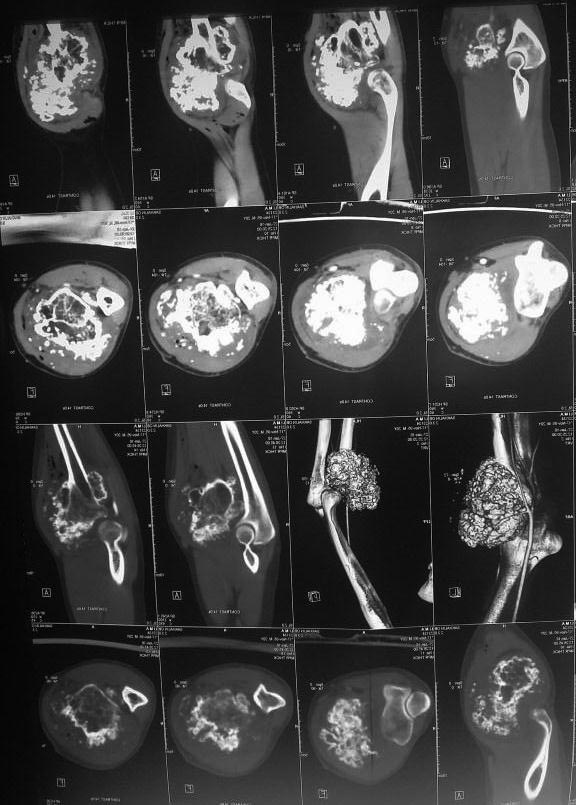

остеохондрома лучевой кости в проксимальном отделе |

Прошу помочь. обратился молодой человек 21 год с образованием правого предплечья. в течении 10 лет рост образования.

Гистологическая верификация - остеохондрома. в течении 2 лет он пытается найти клинику в которой он бы мог лечиться. Через минздрав Сахалинской области были направлены письма в различные клиники России. Отказ получен по всем клиникам кроме Илизарова. Но и там рекомендация по удалению опухоли по месту жительства... Я никогда этим не занимался, и коллеги то же отказываются. Нет опыта в лечении таких пациентов.